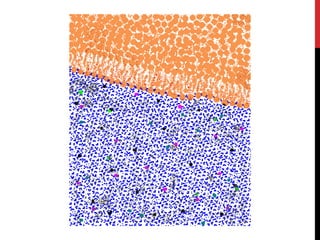

PROTONS ALIGNING WITHIN A MAGNETIC FIELD

• when placed in a magnetic field (B0; e.g., our MRI machines) protons will either align

with the magnetic field or orthogonal to it (process of reaching magnetic equilibrium)

• there is a small difference (10:1 million) in the number of protons in the low and high

energy states – with more in the low state leading to a net magnetization (M)

Inside magnetic field

oriented with or against B0

M = net magnetization

M

Applied Magnetic

Field (B0)

A top that is spinning slightly off the vertical axis is precessing about the vertical axis.

A hydrogen atom precesses about a magnetic field.

All of the hydrogen protons will align with the magnetic field in one direction or the other. The

vast majority cancel each other out, but, as shown here, in any sample there is one or two

"extra" protons.